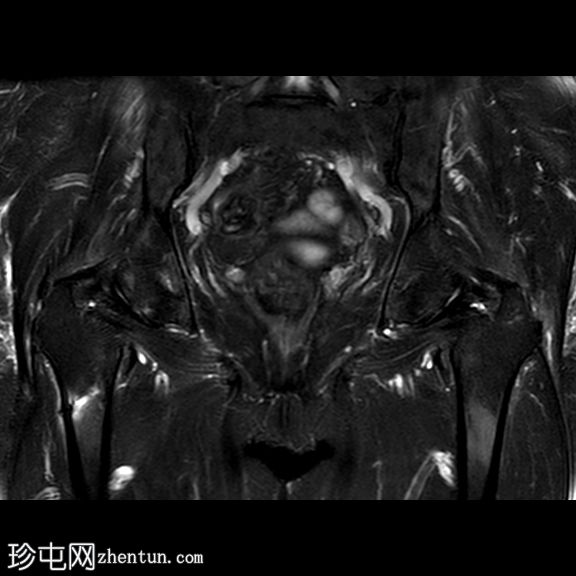

冠状位

T2

一条水平T1和T2低信号骨折线横断右股骨干外侧皮质。近1/3的骨干周长受累,并伴有邻近骨髓水肿。其余皮质骨完整。左股骨未见异常。